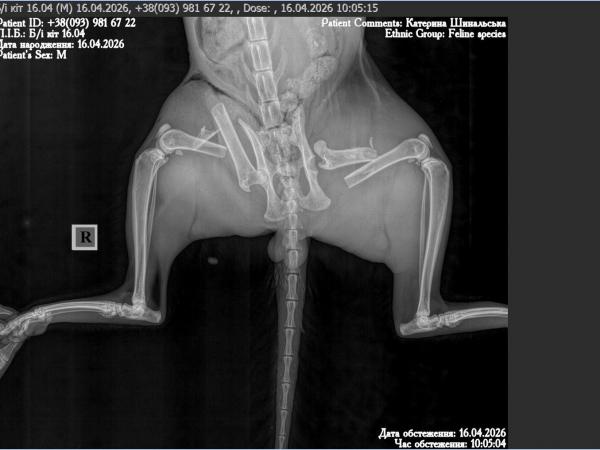

Droga gdzieś w Ukraina i on — małe ciało leżące nieruchomo. Nie ucieka, nie podnosi się, nawet nie próbuje. Obie tylne łapki złamane, biodro przemieszczone. Ciało, które jeszcze chwilę temu było szybkie i żywe, nagle przestaje działać.

Operacja jest długa i skomplikowana. W jego ciele zostaje specjalna konstrukcja, która ma utrzymać kości i dać im szansę się zrosnąć.